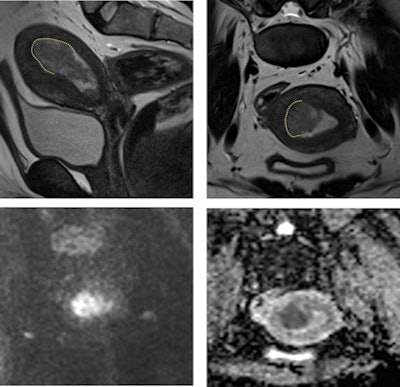

MRI is paramount in excluding myometrial invasion and tumor extension beyond the uterine corpus, according to the authors, who noted that the eligibility criteria for endometrial carcinoma fertility-sparing treatment are the following:

- No contraindications to progestins, no evidence of myometrial invasion on MRI, and no evidence of extrauterine disease on staging with CT or MRI